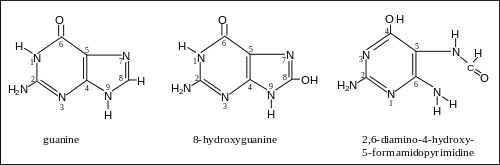

Tobacco smoking is one of the main risk factors for head and neck cancer. A major carcinogenic compound in tobacco smoke is acrylonitrile.[24] Acrylonitrile appears to indirectly cause DNA damage by increasing oxidative stress, leading to increased levels of 8-oxo-2'-deoxyguanosine (8-oxo-dG) and formamidopyrimidine in DNA.[25] (see image). Both 8-oxo-dG and formamidopyrimidine are mutagenic.[26][27] DNA glycosylase NEIL1 prevents mutagenesis by 8-oxo-dG[28] and removes formamidopyrimidines from DNA.[29]